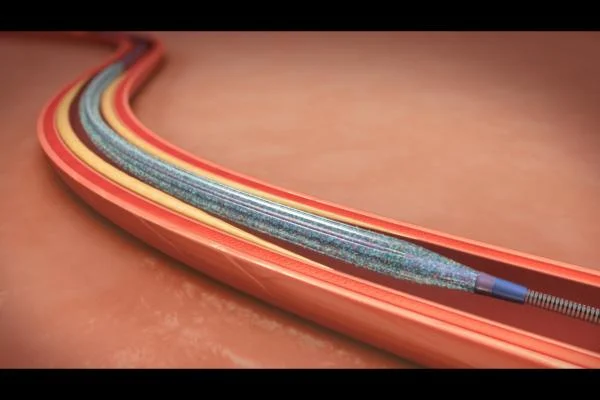

- آنژیوپلاستی کرونری

- آنژیوگرافی کرونری

- گرفتگی رگ ها